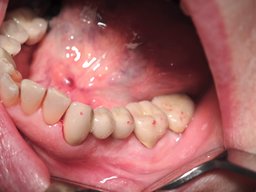

Ergebnis

Nach Einprobe und Freigabe durch den Patienten wird die Brücke zementiert. Das Abschlussfoto zeigt die fertig eingegliederte Versorgung im Mund.